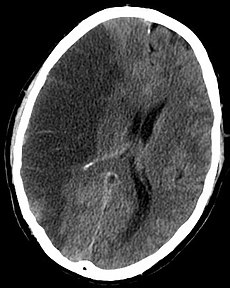

缺血性卒中:主要挑战在所有脑血管疾病中 , 缺血性卒中占了绝大多数 , 大约占卒中病例的70%左右 。 而缺血性卒中的预后较差 , 1年后的致死/致残率约为33.4%~33.8% 。 这意味着患上缺血性卒中的人们更容易陷入生活的困境 。